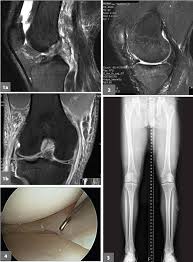

Find side effects and safety information on the official patient site. How long does acl tear surgery recovery take? These are completely normal and usually nothing to worry about: The techniques, medications, and supplements that have been discussed here are convenient and have been used by many people who have undergone acl surgery—with positive results. Numbness numbness around the scars is common due to damage to the small nerves around the knee from the incisions. Although magnetic resonance imaging (mri) creates better images of soft tissues like the acl, according to the american association of orthopedic surgeons, it is usually not required to make the diagnosis of a torn acl.1 There needs to be a balance between trying to do too much work in physical therapy returning strength and range of motion and doing too little. See full list on practicalpainmanagement.com

Sep 12, 2019 · the acl graft, the new ligament, is attached at a steeper angle, which can not only cause rotational instability in the knee but can also disrupt the normal sense of proper position.

It is important when resting with your leg elevated not to have anything underneath your knee as you want to be stretching it out 5. Phase three on the acl surgery recovery timeline is when the knee is most vulnerable. This is taken either from your own tissue (autograft), or from donor tissue (allograft). People usually recover really well after acl surgery, but many report a few problems in the early stages. Knee pain some pain after acl surgery is common both at the knee itself and around the new graft area but it is usually quite tolerable. The alternative methods are listed below. Most patients can expect to play sports and exercise at a high level. The main risks with acl knee surgery are: Acl reconstruction knee surgery involves replacing the torn anterior cruciate ligament with a new graft. Numbness numbness around the scars is common due to damage to the small nerves around the knee from the incisions. It typically takes seven to 10 days after the procedure, until the patient is comfortable without the assistance of a crutch. See full list on practicalpainmanagement.com Discomfort while walking the diagnosis of an acl injury can be confirmed by physical examination, which includes comparing the injured to the uninjured knee to help determine the state of the acl.